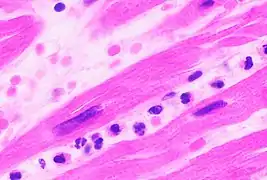

Under the microscope, myocardial infarction presents as a circumscribed area of ischemic, coagulative necrosis (cell death). On gross examination, the infarct is not identifiable within the first 12 hours.[20]

Although earlier changes can be discerned using electron microscopy, one of the earliest changes under a normal microscope are so-called wavy fibers.[21] Subsequently, the myocyte cytoplasm becomes more eosinophilic (pink) and the cells lose their transversal striations, with typical changes and eventually loss of the cell nucleus.[22] The interstitium at the margin of the infarcted area is initially infiltrated with neutrophils, then with lymphocytes and macrophages, who phagocytose ("eat") the myocyte debris. The necrotic area is surrounded and progressively invaded by granulation tissue, which will replace the infarct with a fibrous (collagenous) scar (which are typical steps in wound healing). The interstitial space (the space between cells outside of blood vessels) may be infiltrated with red blood cells.[20]

These features can be recognized in cases where the perfusion was not restored; reperfused infarcts can have other hallmarks, such as contraction band necrosis.[23]

| Myocardial histologic parameters (HE staining)[24] | Earliest manifestation[24] | Full development[24] | Decrease/disappearance[24] | Image |

|---|---|---|---|---|

| Stretched/wavy fibres | 1–2 h |  | ||

| Coagulative necrosis: cytoplasmic hypereosinophilia | 1–3 h | 1–3 days; cytoplasmic hypereosinophilia and loss of striations | > 3 days: disintegration |  |

| Interstitial edema | 4–12 h |  | ||

| Coagulative necrosis: 'nuclear changes' | 12–24 (pyknosis, karyorrhexis) | 1–3 days (loss of nuclei) | Depends on size of infarction |  |

| Neutrophil infiltration | 12–24 h | 1–3 days | 5–7 days |  |

| Karyorrhexis of neutrophils | 1.5–2 days | 3–5 days |  | |

| Macrophages and lymphocytes | 3–5 days | 5–10 days (including 'siderophages') | 10 days to 2 months |  |

| Vessel/endothelial sprouts* | 5–10 days | 10 days–4 weeks | 4 weeks: disappearance of capillaries; some large dilated vessels persist |  |

| Fibroblast and young collagen* | 5–10 days | 2–4 weeks | After 4 weeks; depends on size of infarction; |  |

| Dense fibrosis | 4 weeks | 2–3 months | No |  |